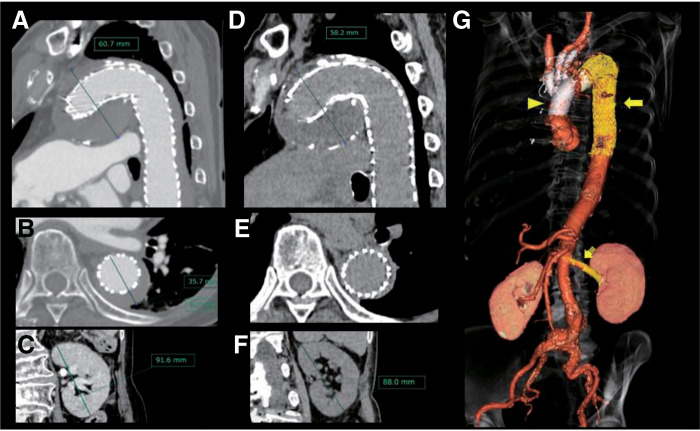

An 84-year-old woman with an acute type B aortic dissection (ATBAD), an entry tear in a distal arch aneurysm, and lower-body malperfusion underwent a hybrid approach combining total arch replacement with an elephant trunk (TAR+ET), thoracic endovascular aortic repair (TEVAR), and left renal artery stenting. This strategy avoided direct resection of the aneurysm or primary entry, yet stabilized hemodynamics and restored organ perfusion. Postoperative CT was favorable, and the patient was discharged without complications. In this elderly case of complicated ATBAD involving a distal aortic arch aneurysm, we performed TAR+ET, TEVAR, and renal artery stenting, and achieved a favorable outcome.

Abstract Image